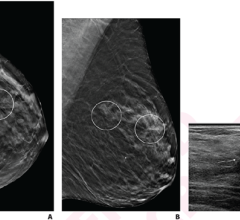

August 29, 2023 — Mammograms are an essential part of preventive healthcare, and when an initial review reveals a ...